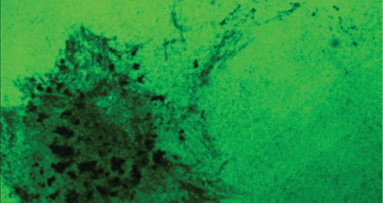

Sin embargo, en un artículo publicado en línea en la revista Aging Cell, los investigadores encontraron que en las células epiteliales que recubren la piel y la boca el nivel de p53 se reduce, en lugar de aumentar, cuando las células envejecen.

Las células epiteliales recubren las principales cavidades del cuerpo, incluyendo la mayoría de los órganos, tales como la boca, el estómago, el intestino delgado, el riñón y el páncreas. Estas células tienen un nivel de p53 que protege de los factores ambientales. Cuanto menor es la cantidad de p53, las células epiteliales de mayor edad tienen más dificultad para mantener la integridad de su material genético cuando se encuentran con agentes carcinógenos, lo que permite que el cáncer se desarrolle.

Park y su equipo informaron que en los seres humanos el nivel de p53 en la piel y las células epiteliales de la boca disminuyó con la edad por factores epigenéticos (externos y ambientales), no por cambios en la secuencia del ADN de la p53.

"Puesto que aproximadamente el 90% de los cánceres humanos se originan a partir de células epiteliales, sospechamos que esto puede tener que ver con el aumento de la incidencia cánceres de piel y orales en pacientes de edad avanzada", dijo el Dr. Reuben Kim, profesor asociado de Odontología en UCLA y coautor del estudio.